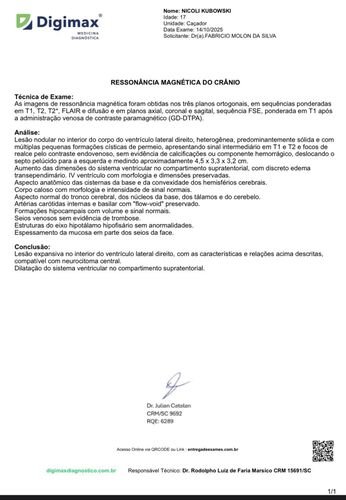

Estamos iniciando esta campanha com um único objetivo: arrecadar recursos para que a Nicoli possa realizar uma cirurgia delicada no cérebro. Recentemente, ela foi diagnosticada com um tumor cerebral, que requer avaliação especializada e procedimento cirúrgico com urgência.